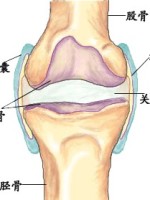

顾名思义,关节滑膜炎是关节滑膜的炎症,所以要明白什么是滑膜炎,首先需要大家大概的了解一下关节的解剖结构。我们都知道关节是由骨、软骨、滑膜、肌肉、韧带、肌腱共同构成的一个复杂结构,内部有狭窄的间隙,我们叫做关节腔。

关节滑膜就是关节腔的内衬,如同一间屋子里的墙纸一样,不仅可以维护关节的完整性,缓冲关节受到的各个方向的冲击,还能够持续不断的分泌滑液,这些滑液存在于骨与软骨的表面,在运动过程中,起到润滑关节、减少摩擦的重要作用。

在人体的诸多关节中,以膝关节的结构最为复杂、关节内的腔隙最大、滑膜组织最为丰富,加之膝关节几乎是日常活动中使用频率最高的关节,因此膝关节滑膜受到损伤的几率最大,这也就解释了为什么关节滑膜炎最多见于膝关节。而在小儿疾病中,髋关节的滑膜炎也比较常见。